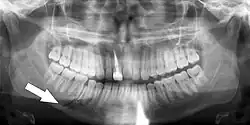

Panoramic radiographs have the capability to demonstrate a portion of the neck and display atheromas (calcifications in the carotid artery) which are an indication of both local and generalized (systemic) atherosclerosis. Atherosclerosis of the coronary arteries leading to myocardial infarction (heart attack), and atherosclerosis of the carotid artery leading to stroke are the number one and number three most common causes of death in the United States.[6]

There is interest to look at panoramic radiographs as a screening tool, however further data is needed with regards if it is able to make a meaningful difference in outcomes.[7]

Epidemiology: general public and high risk groups

Additional research projects have further determined the prevalence rate of these atheromas in the general population (3–5%)[8][9] and among high-risk groups (over 25% in: recent stroke victims,[10] individuals with obstructive sleep apnea syndrome,[11][12][13] postmenopausal women,[14] type 2 diabetics,[15][13][16] individuals with dilated cardiomyopathy,[17][13] and among individuals who have received radiotherapy directed at the neck,[18][19]). These findings have been corroborated by other several other researchers.[20][21][22][23][13]

Atherosclerosis is attributed to risk factors that include cigarette smoking, hyperlipidemia, obesity, diabetes mellitus, and hypertension (high blood pressure). These factors, however, do not fully account for the risk of disease. Atherosclerosis has been conceptualized as a chronic inflammatory response to endothelial cell injury[24] and dysfunction possibly arising from chronic dental infection. In 2010, using the previously validated Mattila panoramic radiographic index to quantify the totality of dental infection (i.e., periapical and furcal lesions, pericoronitis sites, carious tooth roots, teeth with pulpal caries, and vertical bony defects), Friedlander's group determined that individuals with carotid artery atheromas on their panoramic radiographs had significantly greater amounts of dental infection/inflammation than atherogenic risk-matched controls devoid of radiographic atheromas.[25][26] While the Mattila index had been previously used to relate the extent of dental infection to coronary artery disease, this research is the first to link the full range of dental disease that it measures to panoramic radiographs evidencing calcified carotid artery atherosclerosis.